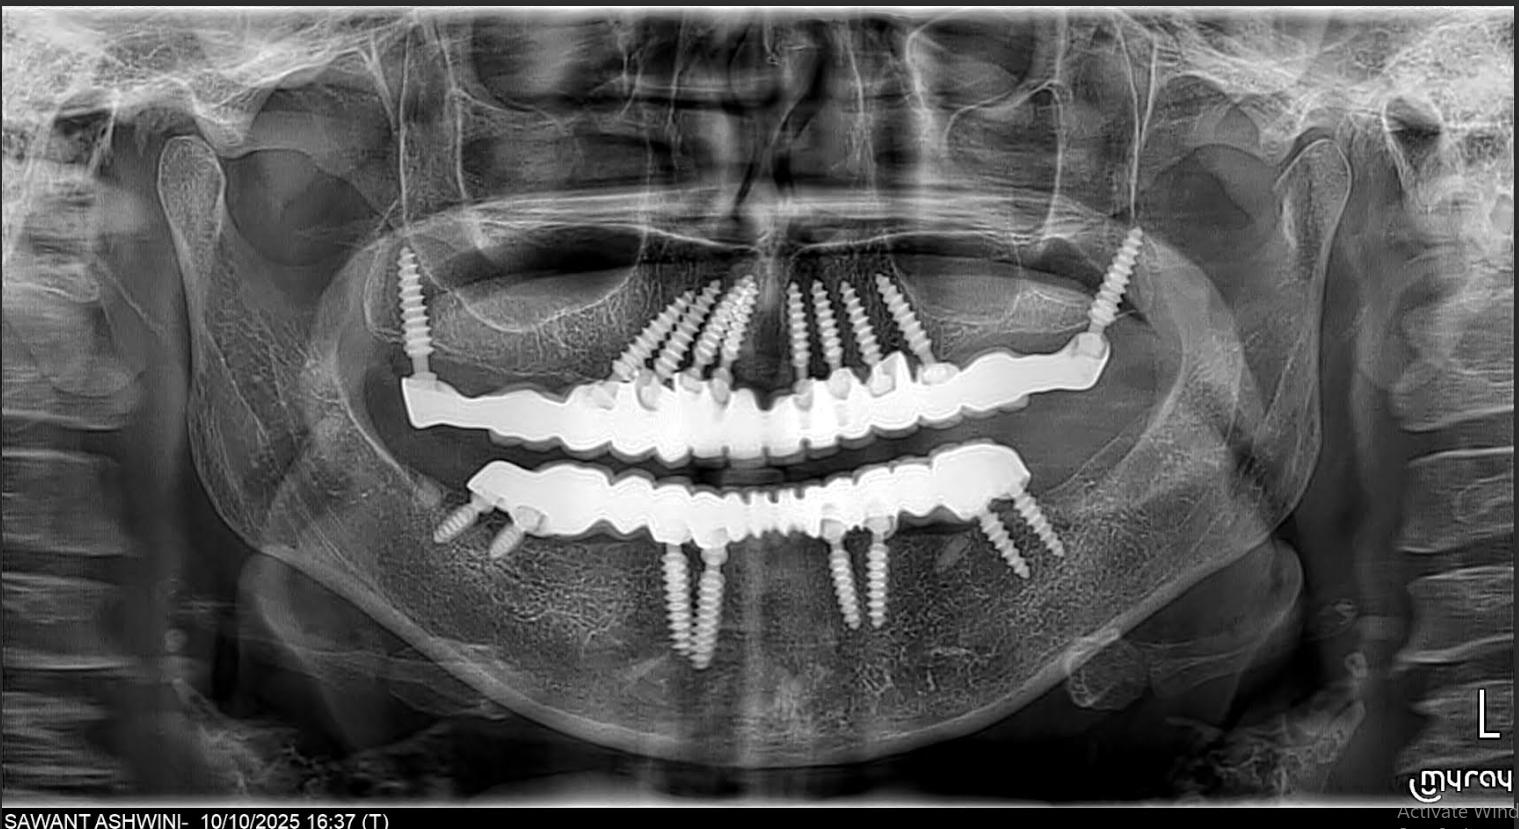

X-Ray Analysis

OPG — After

Radiographic Findings

The post-treatment OPG shows well-placed implants in both upper and lower jaws, providing strong support for fixed prosthesis. This confirms successful implant placement and immediate loading capability.